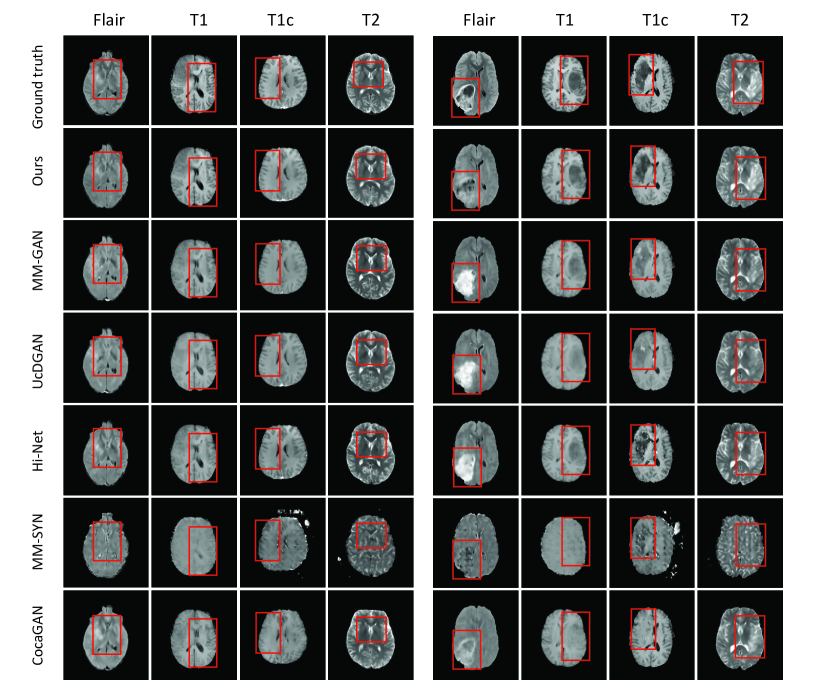

Figure 2: Visual comparison of synthesized MRI image. The left panel shows representative synthesis results with relatively benign tumors, while the right panels shows results with more malignant tumors. The columns of each panel from left to right show Flair, T1, T1c, and T2 images. The rows from bottom to up denote the synthesis results of different methods, i.e., CocaGAN, MM-SYN, Hi-Net, UcDGAN, MM-GAN, Ours, and the ground truth (the top row).

3.2.2 Qualitative results.

For visual evaluation, Fig. 2 demonstrates two sets of representative synthesized images of various missing modalities using different conditional generative methods. The left and right panel show results with benign and malignant tumors, respectively. It can be seen that UMM-CSGM can provide more structural details and clearer textural features in the brain tissue, which can be more prominently appreciated in the T1 images of benign tumor (the second column in Fig. 2). It places a much clearer description of the gray and white matters as notified in the red box, i.e., the gray and white matter are more distinctive. More importantly, our method performs better in the lesion area affected by malignant tumors. Particularly, the tumor-affected areas can sometimes present themselves as brighter contrast and sometimes darker contrast in Flair images (the seventh column in Fig. 2). Existing methods have problem handling such diversity, leading to artificial signal enhancement in the lesion. In contrast, our method can perform significantly better, without implementing spatial attentions, extracting complex textural features, or demanding more conditional information compared to competing methods. The better cross-modal dependence modeling ability of UMM-CSGM itself can automatically address the requirement of diversity.